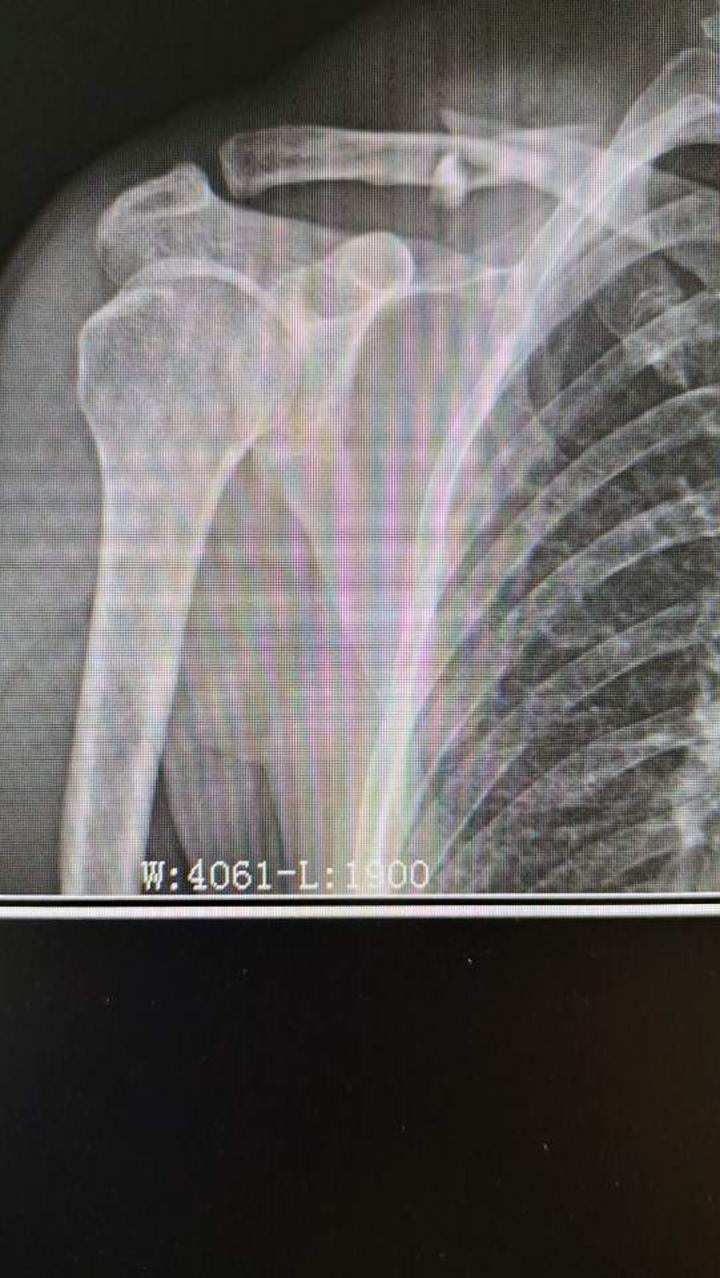

左锁骨骨折